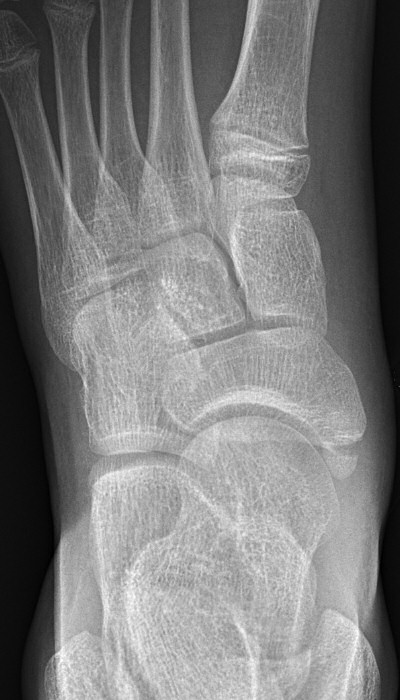

Första bilden med normal navikulare, andra bilden med accessorisk navikulare typ 2, tredje bilden typ 3.